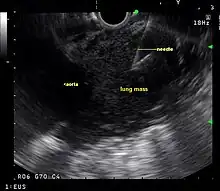

Endoscopic ultrasound (EUS) is an endoscopic technique where a miniaturized ultrasound probe is passed through the mouth into the upper gastrointestinal tract to investigate organs and structures close to the esophagus, stomach, or duodenum, such as the lung. In 1993, Wiersema published the first description of EUS to diagnose and stage lung cancer,[27] done by advancing a fine needle through the esophagus into adjacent lymph nodes. Numerous subsequent studies have shown this general methodology to be effective, very safe, minimally invasive, and very well tolerated. Given these advantages, many authorities think that EUS together with endobronchial ultrasound (EBUS) enhances lung cancer diagnosis and staging.[28]

Endoscopic ultrasound (EUS)

A metaanalysis published in 2007, based on 1,201 cancers in 18 high-quality clinical trials carefully selected by predefined criteria from the literature, systematically examined the performance of EUS-guided FNA in NSCLC staging. Two scenarios were considered: the setting of enlarged lymph nodes on CT (suggestive but not diagnostic of cancer), and the obverse scenario of an absence of lymph node enlargement on CT (suggestive but not diagnostic of no cancer).[24] Overall, in both settings, minor complications were reported in 0.8% of procedures; no major complications were recorded. EUS-FNA in enlarged discrete mediastinal lymph nodes had an excellent pooled sensitivity (8 studies) of 90% (95% CI, 84 to 94%) and specificity of 97% (95% CI, 95 to 98%). EUS-FNA in the setting of no enlarged mediastinal lymph nodes on CT had a pooled sensitivity (4 studies) of 58% (95% CI, 39 to 75%) and specificity of 98% (95% CI, 96 to 99%). Although this sensitivity (58% in CT-negative disease) might on first consideration seem disappointing, if EUS is performed as a staging test it can help avoid more invasive staging procedures, or surgery, if positive (for the presence of cancer). In other words, an EUS that has a positive result (shows cancer) will avoid further needless surgery, whereas a result not showing cancer may be false-negative, and probably requires an excisional biopsy technique for confirmation, such as VATS or mediastinoscopy.

EUS can reliably reach the lymph node stations 5, 7, 8 and 9. In the superior mediastinum the trachea is somewhat to the right of the esophagus which makes it often possible to reach left-sided area 2 and 4 lymph nodes and, less often, right sided paratracheal lymph nodes.[29] In general, EUS is most appropriate for evaluation of the posterior inferior mediastinum while mediastinoscopy or EBUS are best for the anterior superior mediastinum. The feasibility of EUS-FNA of aorto-pulmonary space (subaortic) lymph nodes (station 5) is a major advantage of EUS. Evaluation of this station has traditionally required a paramedian mediastinotomy (Chamberlain procedure). EUS can easily sample celiac lymph nodes, which cannot be reached by the other mediastinal staging methods. In one recent study an unexpectedly high incidence of celiac lymph node metastasis (11%) was noted.[30] EUS can also be used to biopsy potential left adrenal metastases, whereas the right adrenal gland is mostly inaccessible.[31]